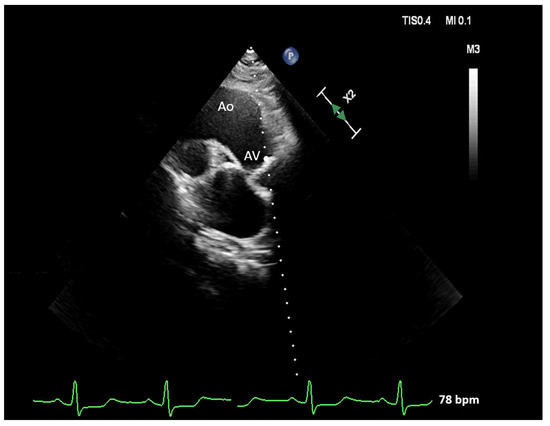

| Aortoseptal angle, ° | 124 [118; 132] | 114 [110; 117] | <0.001 * |

| Doppler intercept angle in A5C, ° | 18.8 [12.6; 26.0] | 30.6 [27.5; 34.6] | <0.001 * |